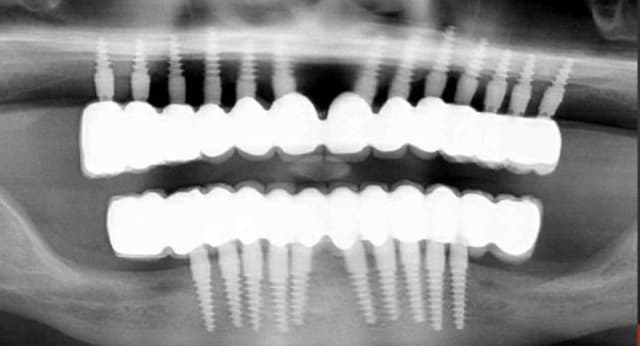

A défaut d'une chir en direct .. voilà une petite histoire en photos ou comment en 90 minutes passer d'un partiel résine à ...7 implants sur provisoires..stabilité primaire 60N grace à la technique MIMI ( oui.. post spécial ce Week end)..:)

Maintenant concernant la demande de scans : je poste ce cas, une patiente vient me voir avec son scan car elle a consulté d'autres "spécialistes" et on lui refuse la pose d'implant secteur 4 où alors avec greffe préalable..Ca se discute..pas de temps à perdre je sais faire autrement..

Avec la chir trans gingivale technique MIMI ( Oui..un post sur la technique bientôt ..) j'ai pu placer deux 3,5/8mm..aurai je eu le meme résultat avec un lambeau..j'en doute..Les couronnes sont en titane. Recul clinique 2 ans ras. Simple efficace rapide moins onéreux satisfaisant pour le praticien et la patiente..